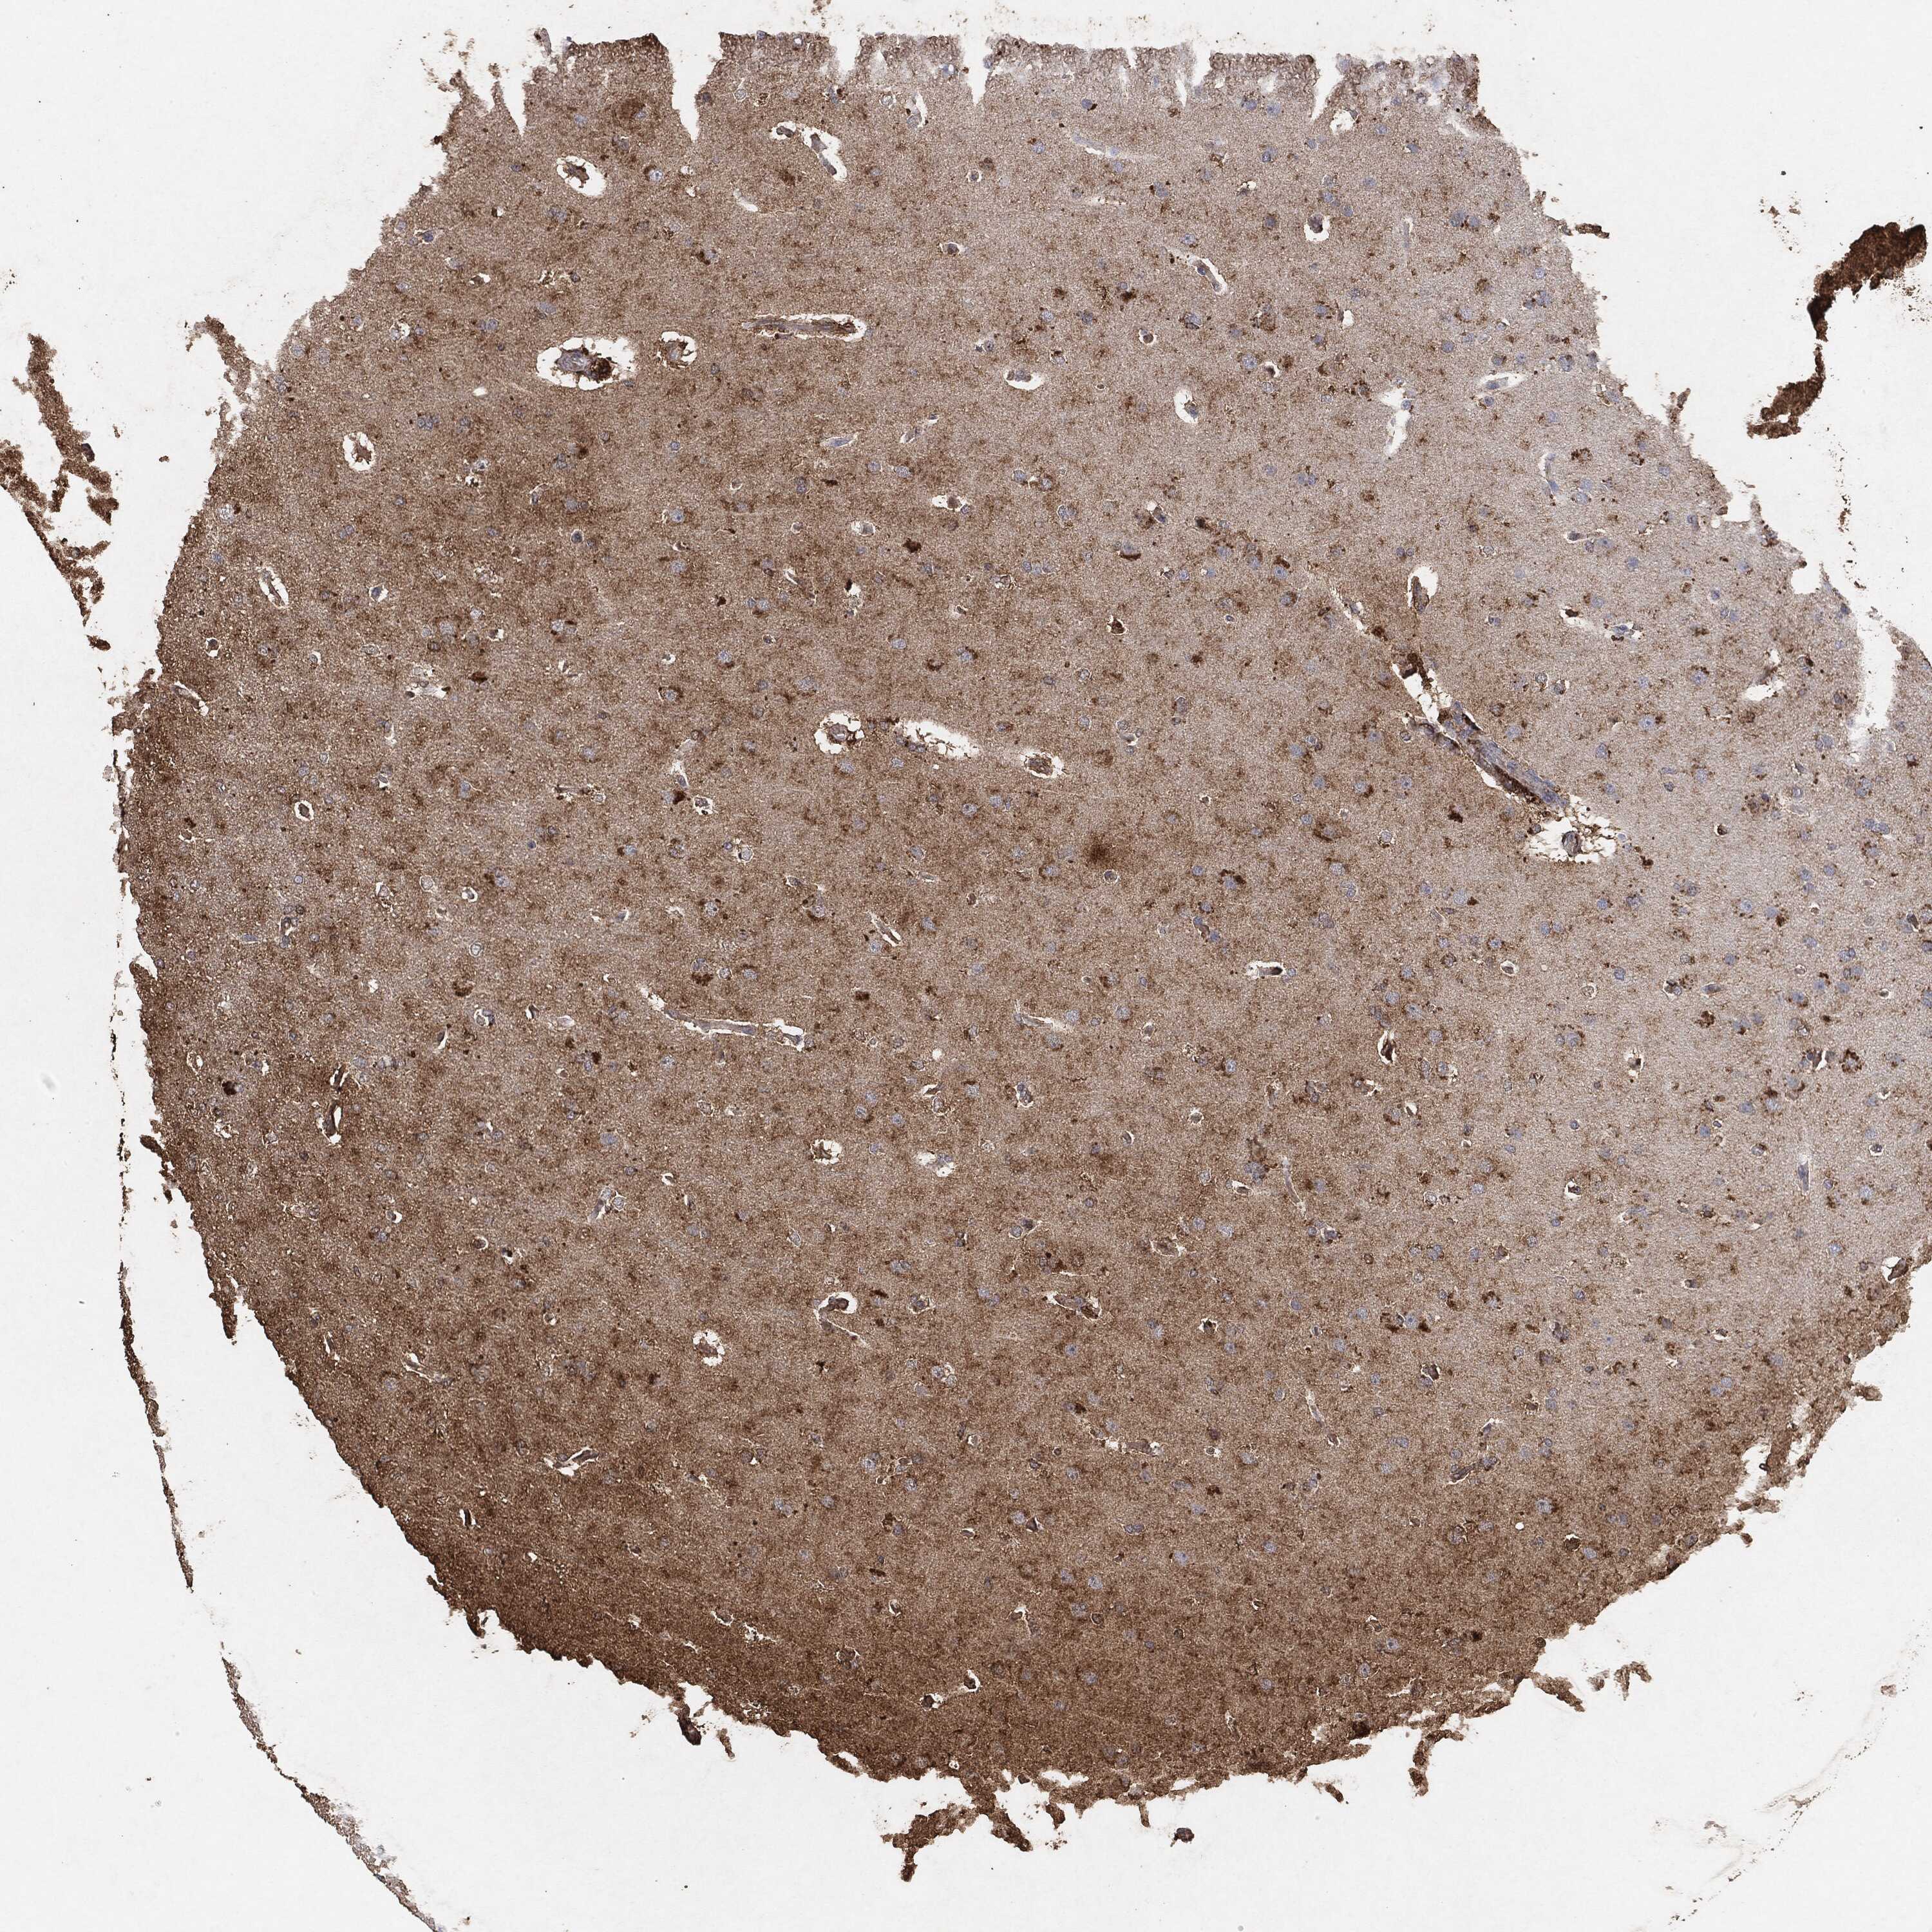

GLIOMA - Protein expressioni

A mouse-over function shows sample information and annotation data. Click on an image to view it in a full screen mode. Samples can be filtered based on level of antibody staining by selecting one or several of the following categories: high, medium, low and not detected. The assay and annotation is described here.

Note that samples used for immunohistochemistry by the Human Protein Atlas do not correspond to samples in the TCGA dataset.

Antibody stainingi

Antibody staining in the annotated cell types in the current human tissue is reported as not detected, low, medium, or high, based on conventional immunohistochemistry profiling in selected tissues. This score is based on the combination of the staining intensity and fraction of stained cells.

Each image is clickable and will lead to virtual microscopy that enables deeper exploration of all samples and also displays staining intensity scores, fraction scores and subcellular localization as well as patient and tissue information for each sample.

Glioma, malignant, High grade

Glioma, malignant, Low grade

Glioma, malignant, NOS